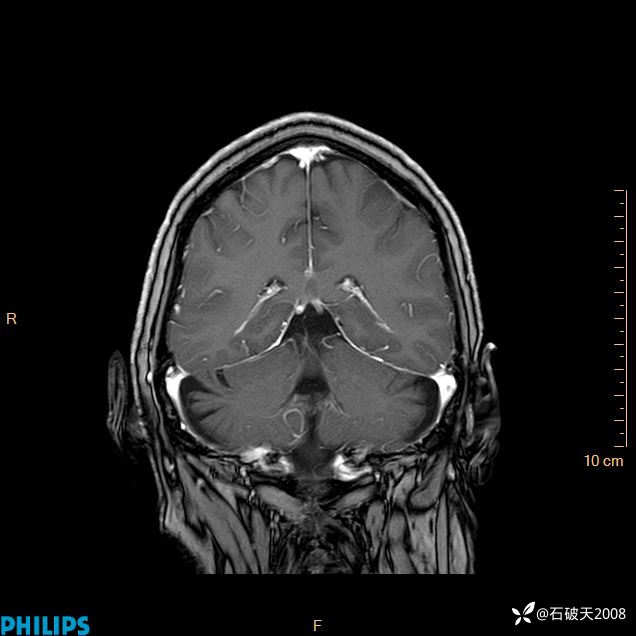

2024.2.21MR

增强冠状位